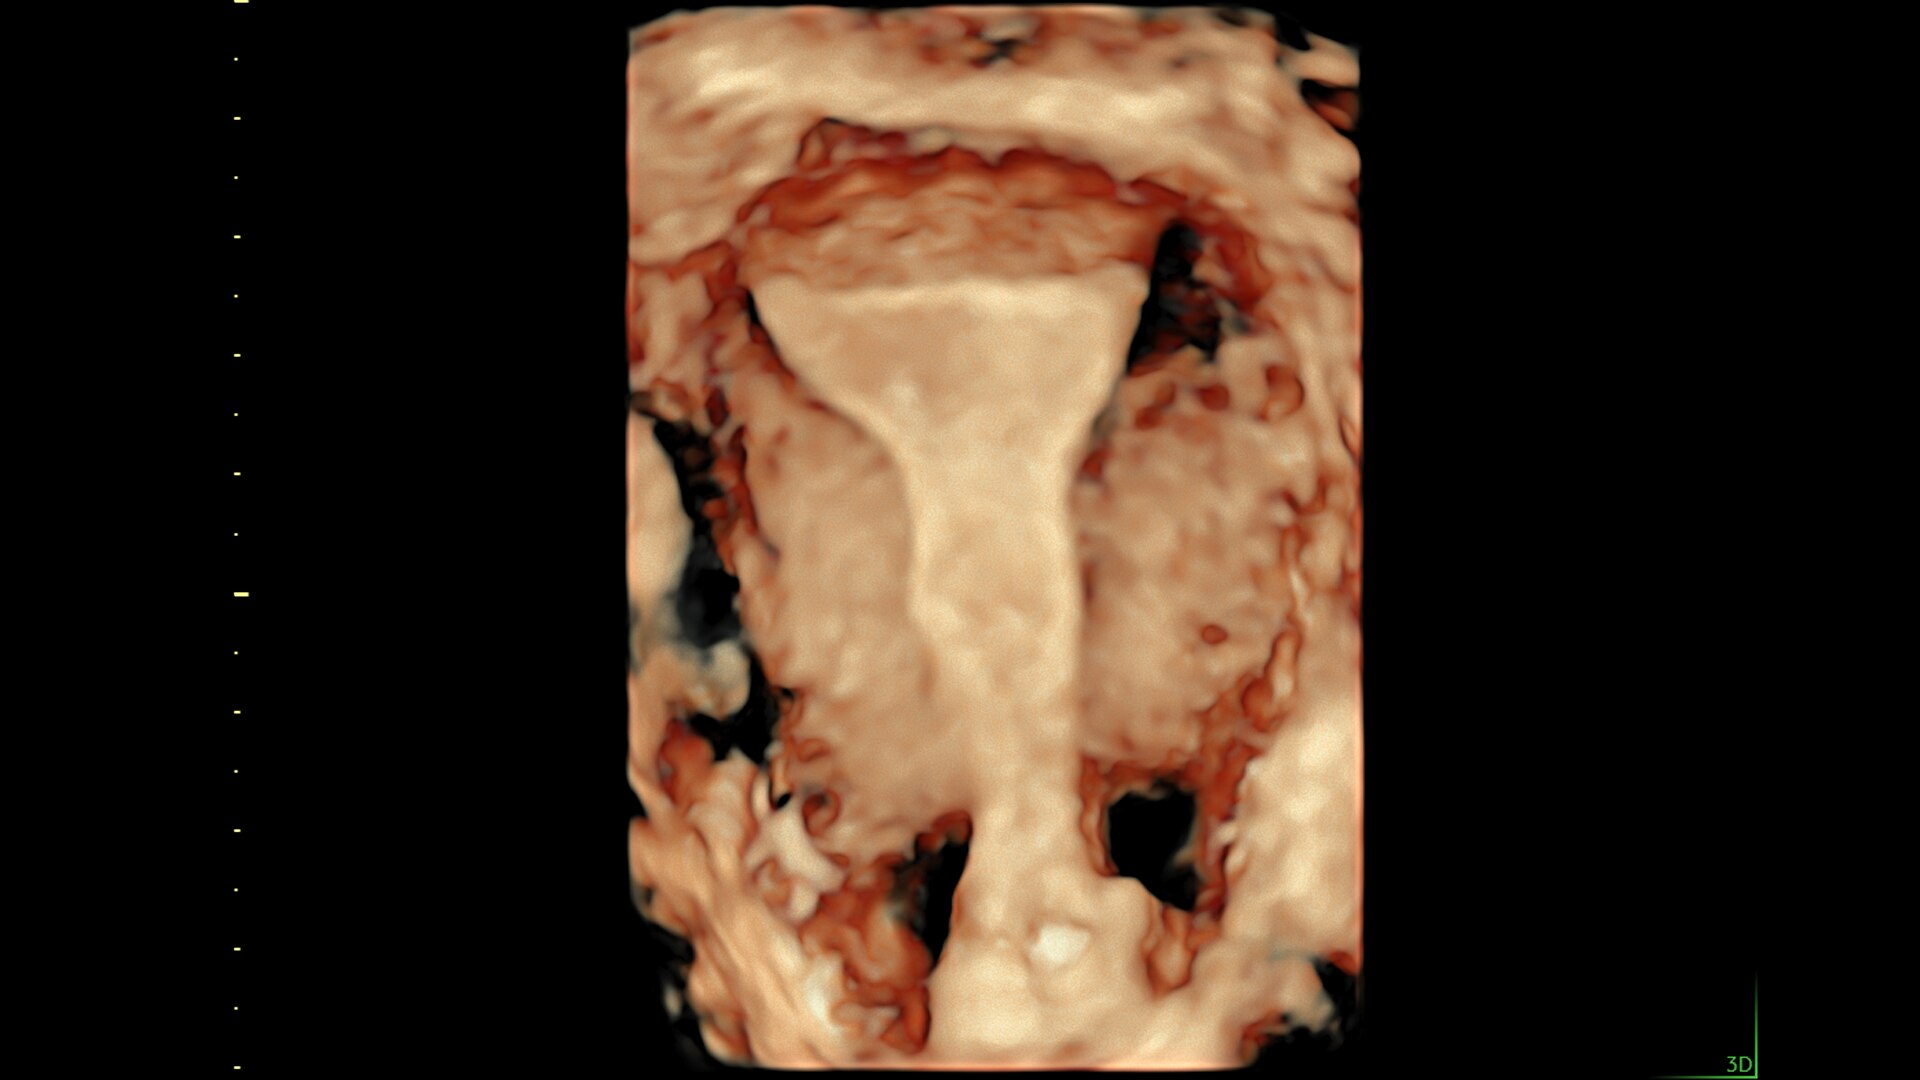

SonoGYN

Combines our Uterine Trace tool and Fibroid Mapping feature, an AI reporting tool that standardizes and streamlines fibroid documentation by mapping, measuring, and classifying fibroids in 3D.